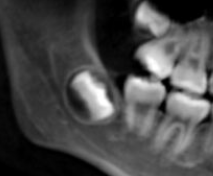

しかし、現代人は顎が小さくなっているため、親知らずがきれいに生えるスペースが足りないケースが非常に多いのが現状。その結果、

- 横向きに生える(水平埋伏)

- 一部だけ出てくる(半埋伏)

- 他の歯を押すように成長する

などのトラブルを引き起こすこともあります。

◎ 親知らずが完全に骨の中に埋まっていて、動く気配がない

レントゲン検査で確認した結果、親知らずが骨の中に完全に埋まっており、周囲の歯に影響しないと判断された場合は、経過観察になります。